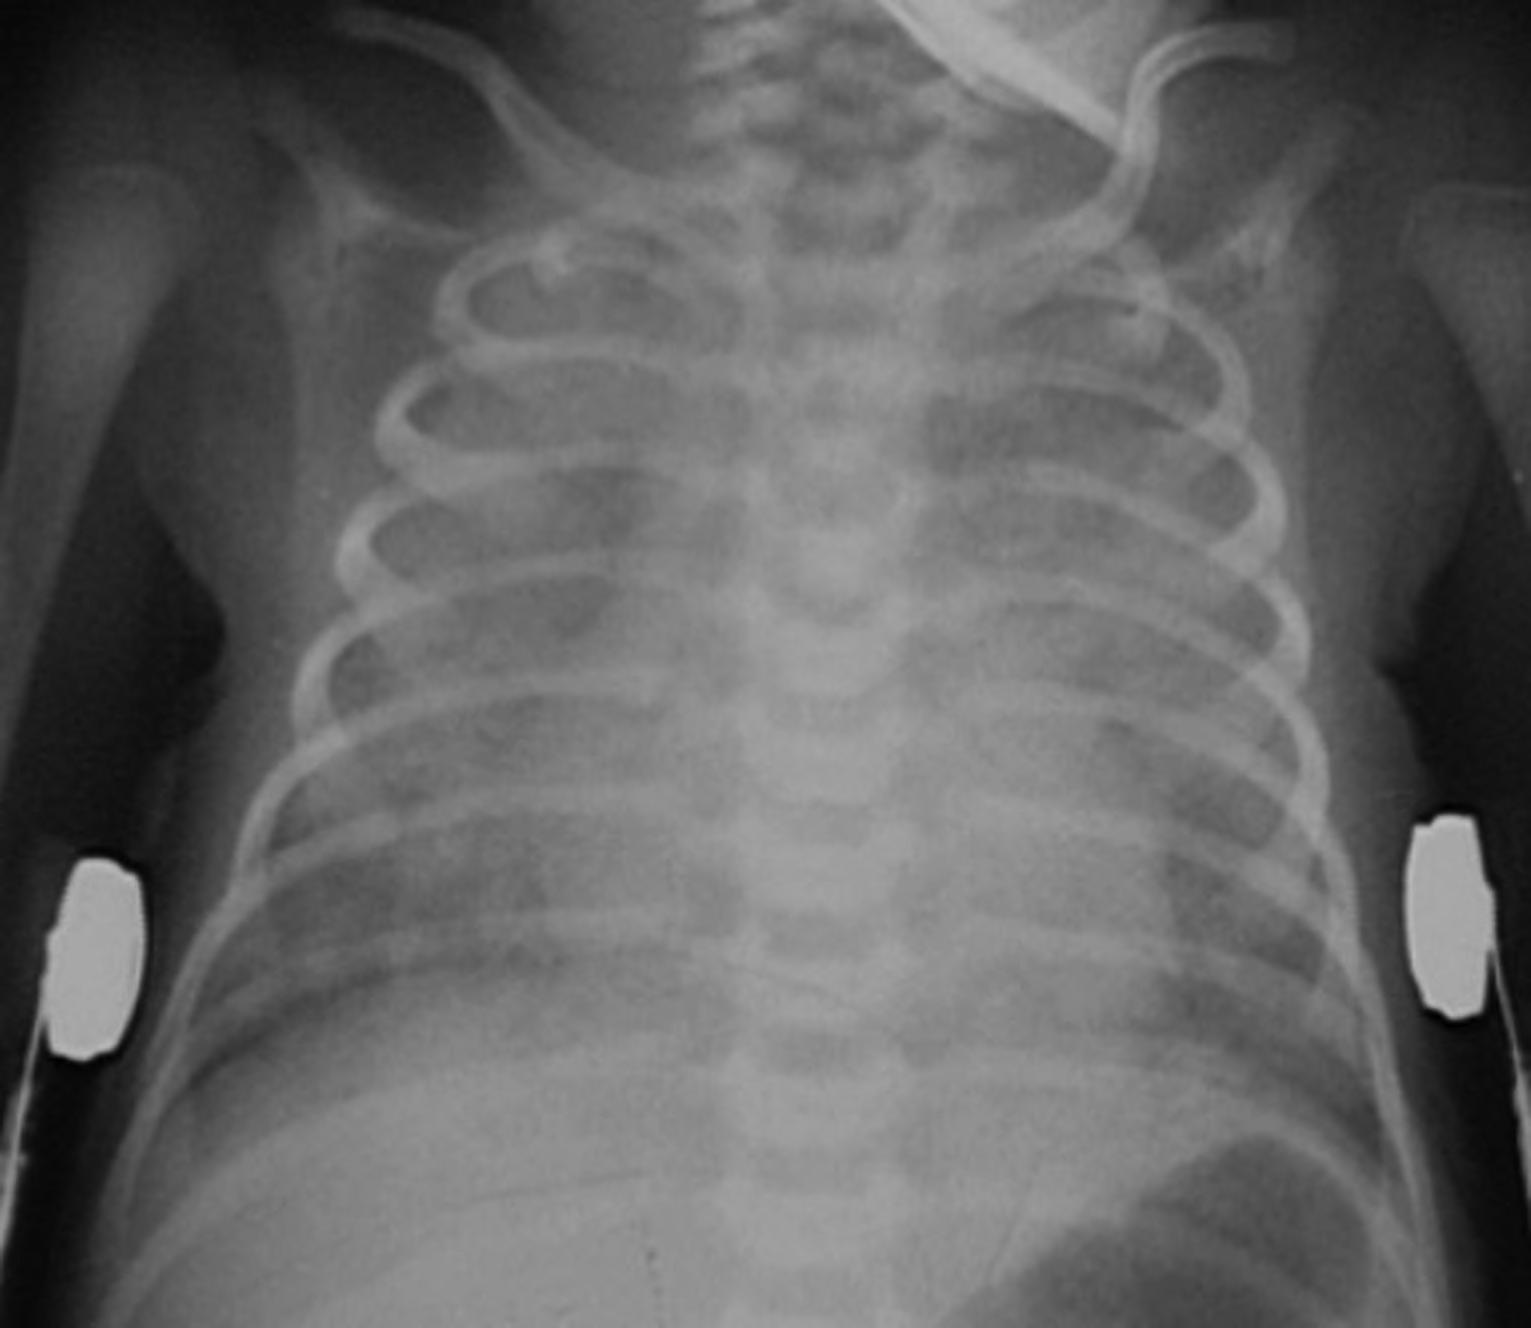

Careful attention to the heart, mediastinum, airway, lungs, pleura, bones, and soft tissues is essential to accurately diagnose the cause of chest pain. A screening chest film for patients with chest pain has low sensitivity for structural cardiovascular lesions, such as myocarditis, dissection, or pulmonary infarction, but is helpful in the acute setting to diagnose complications of underlying cardiovascular conditions, such as HF, mediastinal hematoma, or pulmonary infarction. It is also helpful to exclude noncardiac causes of chest pain, including pneumonia, pneumothorax, rib fracture, or an aspirated foreign body (see normal chest radiograph, Figures 1.2a and 1.2b).

FIGURES 1.2 a AND 1.2 b PA and lateral views of the chest in a normal 16-year-old for comparison (different patient). Note the normal appearance of structures. Contour of descending aorta (white arrowheads), superior mediastinal width between superior vena cava on the right and aortic arch on the left (white thick arrows on right and left side), tracheal air column (black arrow), carina (black arrowhead), and the orientation of the clavicles (thin white arrows). In a properly positioned patient the spinous processes lie midway between the medial ends of the clavicles. The cardiothoracic ratio is measured as the ratio of the cardiac transverse diameter (black thin line) divided by the maximum chest transverse diameter (thick black line). The first and second ribs on the left side are numbered (1, 2).